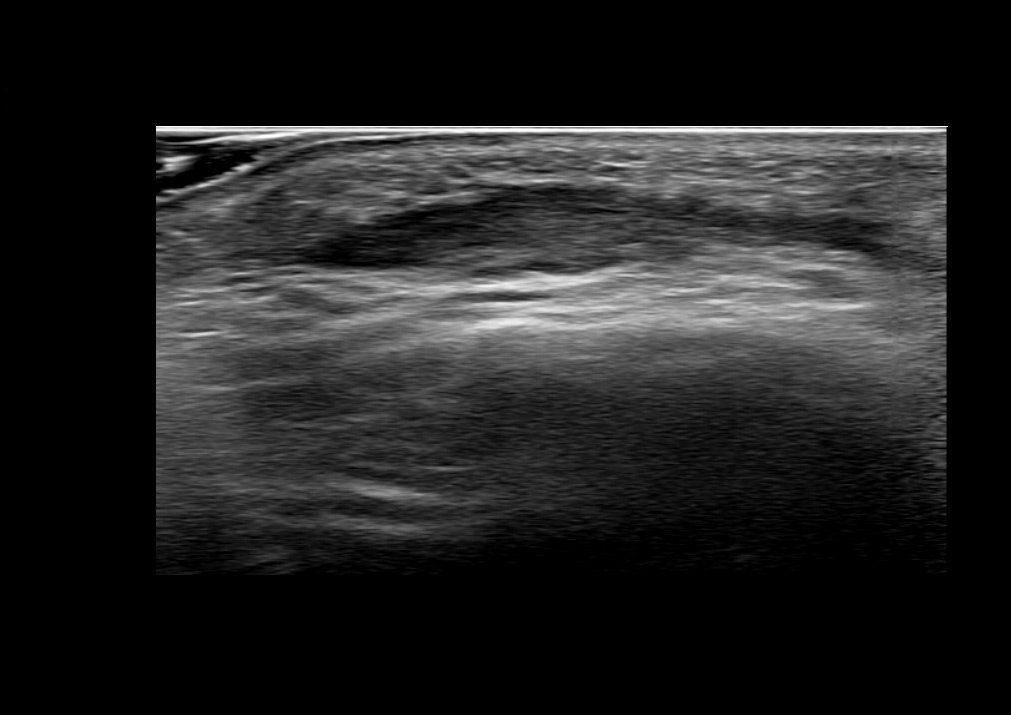

Study the first image to recognize the different layers. If you are sure about the layers, swipe to the second image to view the answer (if applicable).